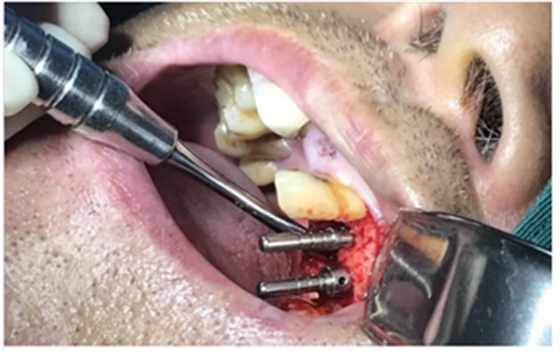

使用種植導(dǎo)板專用手術(shù)器械完成種植位點(diǎn)逐級(jí)備洞

進(jìn)行精準(zhǔn)測(cè)量

植體置入

愈合基臺(tái)的置入及縫合